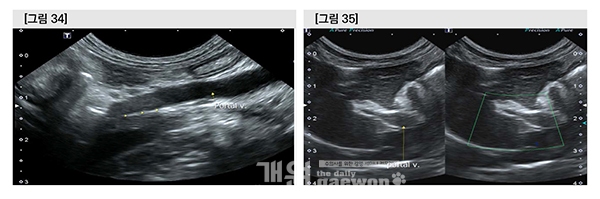

수술 이틀째 gastroduodenal v.에서 hepatofugal flow와 hepatopetel flow가 호흡에 따라 alternation 되고 있었으나 splenic v.에서는 consistent hepatofugal flow였고, 간으로 insertion 하기 직전의 portal vein을 flow velocity는 거의 측정되지 않았으므로 여전히 문맥혈액은 간을 우회(bypass)하고 있다고 판단하였다.

수술 4일째 portal v.에서 thrombus 의심 물질이 관찰되었고, PV의 blood flow는 측정되지 않았다. Splenic v.의 blood flow는 hepatofugal과 hepatopetal flow가 번갈아 가며 관찰 되었으나 gastroduodenal v.은 지속적으로 hepatofugal flow였다. Portal vein 내의 thrombus 형성과 함께 문맥 혈액은 splenic v.과 gastroduodenal v.으로 우회하고 있었다.